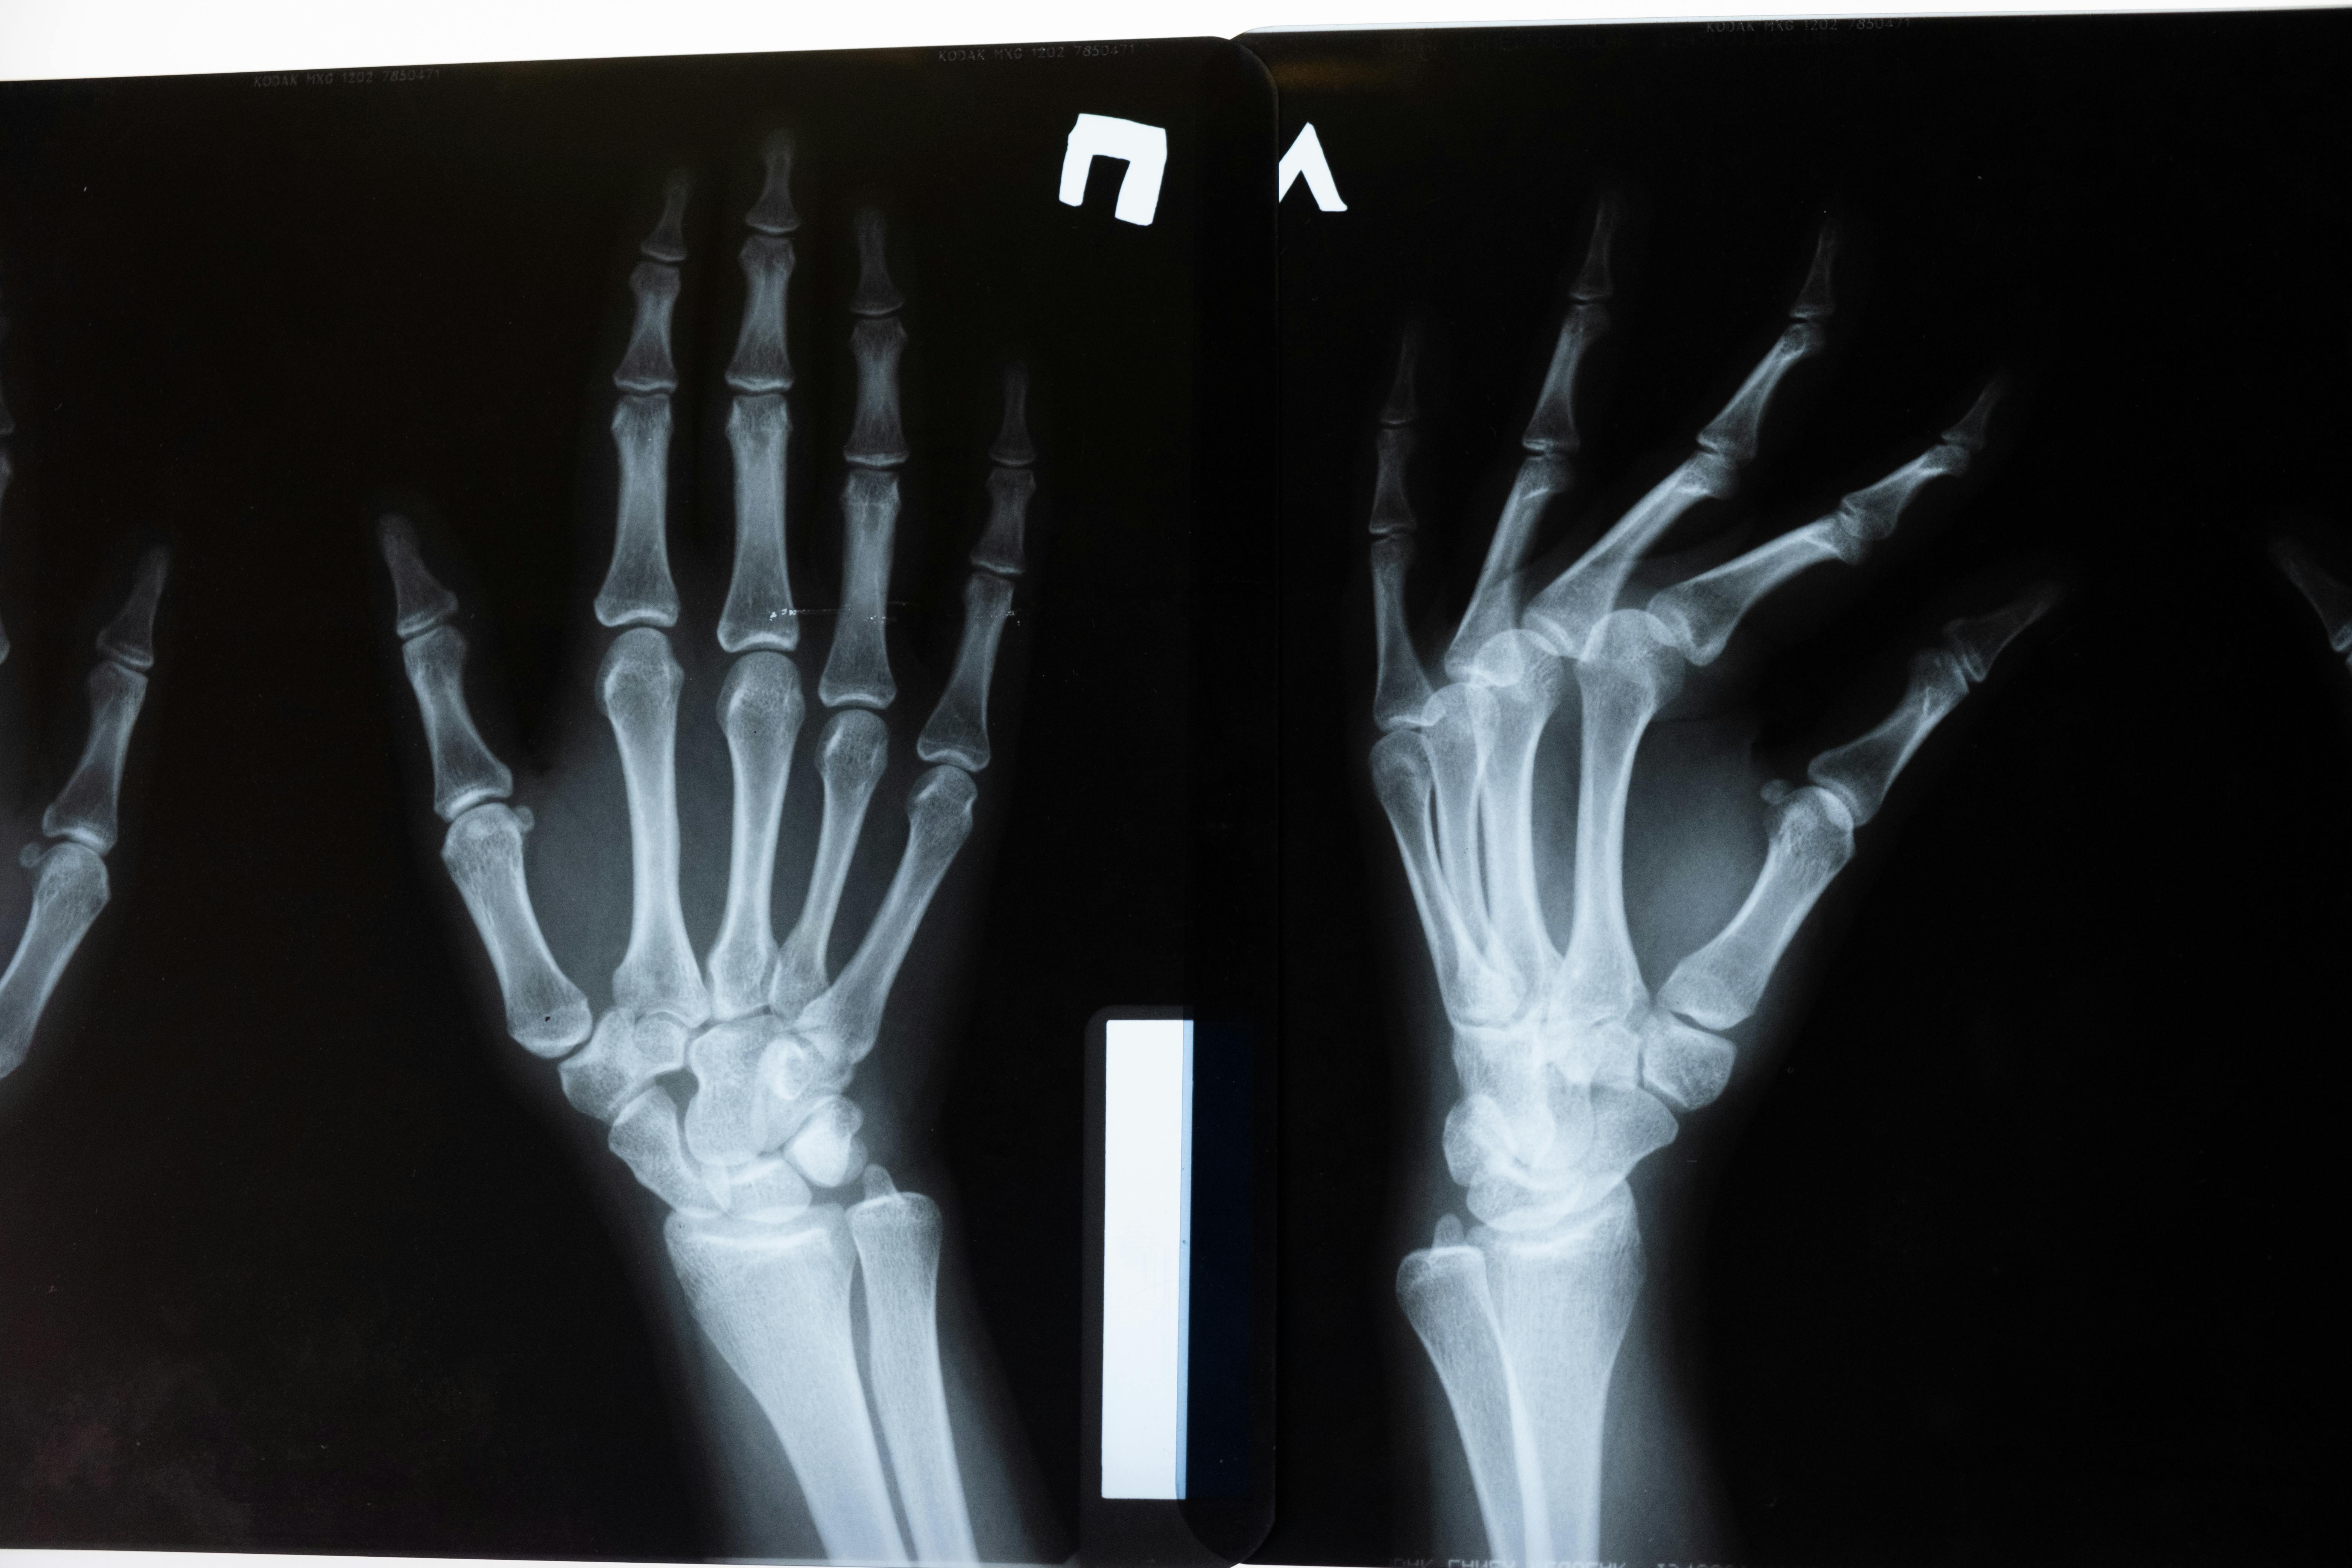

정형외과나 재활의학과에서 관절 상태를 주기적으로 확인하고, 염증 여부나 퇴행 정도에 따라 적절한 치료를 받는 것이 중요합니다.